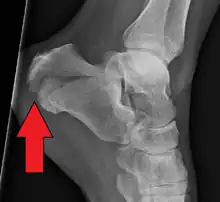

| X-ray of a fractured calcaneus | |

The Angle of Gissane, or "Critical Angle", is the angle formed by the downward and upward slopes of the calcaneal superior surface. On a lateral radiograph, an angle of Gissane > 130° suggests fracture of the posterior subtalar joint surface. Böhler's angle, or the "Tuber Angle", is another normal anatomic landmark seen in lateral radiographs. It is formed by the intersection of 1) a line from the highest point of the posterior articular facet to the highest point of the posterior tuberosity, and 2) a line from the former to the highest point on the anterior articular facet. Böhler's angle is normally 25° to 40°.[14] It is named after Austrian physician Lorenz Böhler.[16] A decreased angle is indicative of a calcaneal fracture.